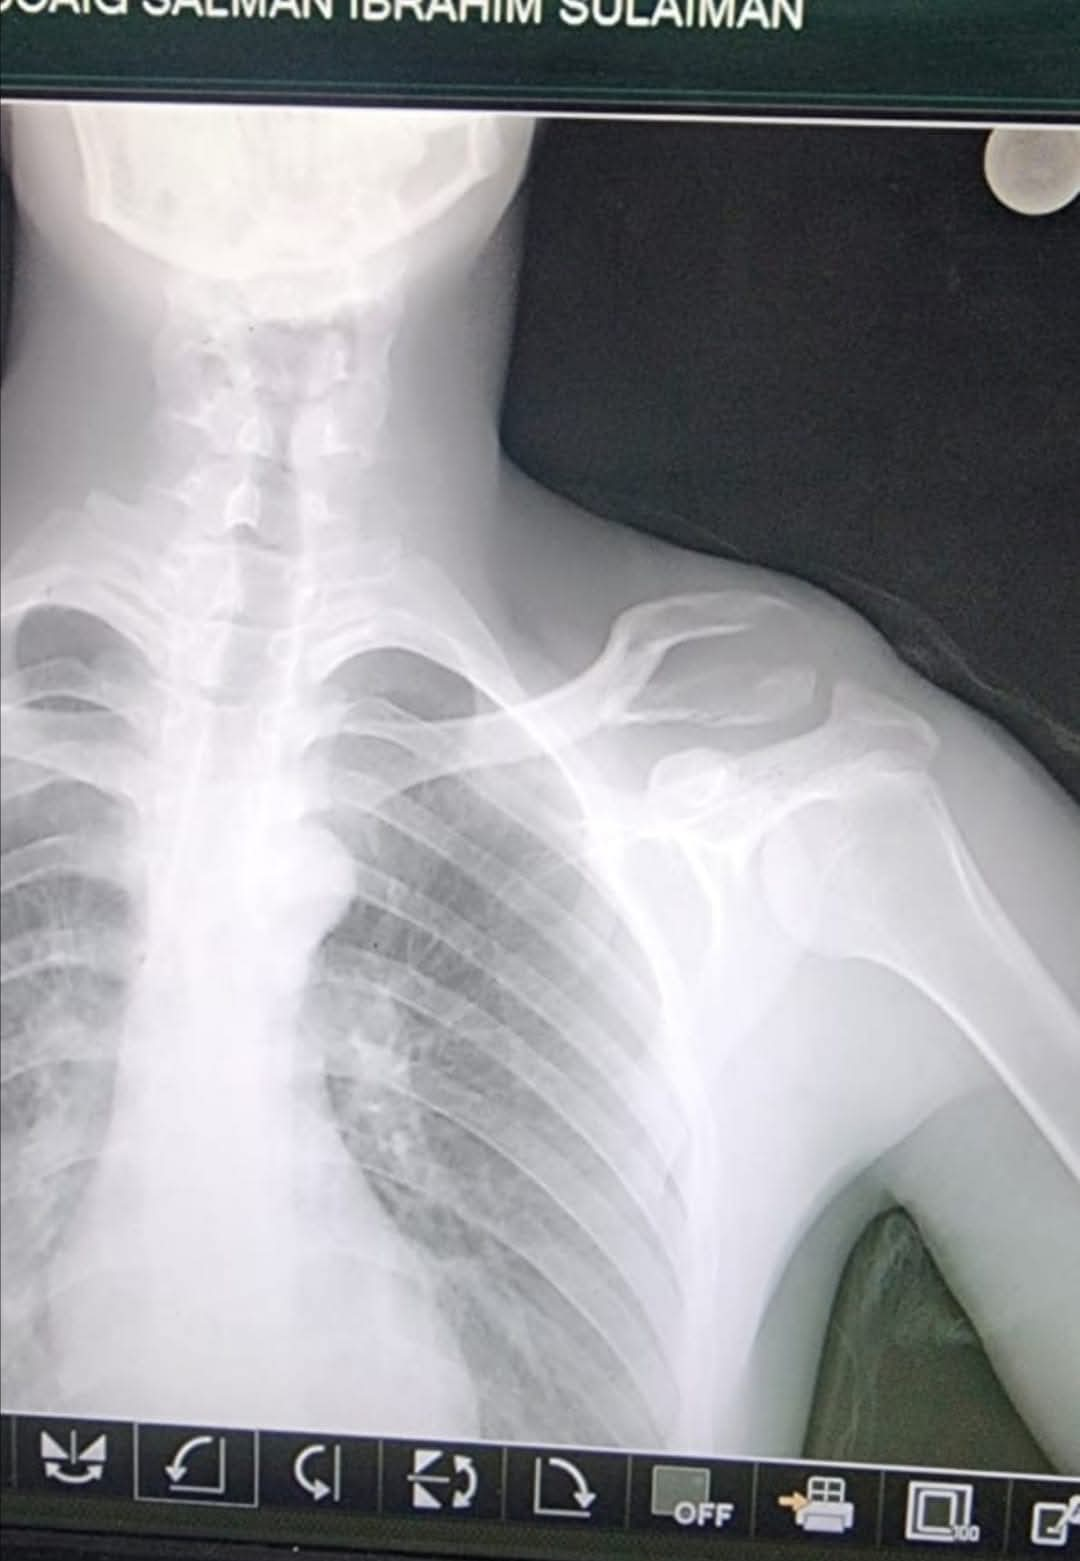

وطنا اليوم -  يقوم بعمليات تثبيت الكسور المعقدة بشكل طاريء وتبديل المفاصل بشكل مبرمج  مما خفف على المواطنين البحث عن أسرة في مستشفيات مركزية رغم صعوبة عمليات العظام من الناحية التقنية في المستشفيات النائية  إضافة الى  استقبال اعداد كبيرة بالعيادات ومعالجة جميع المرضى بالطرق المثلى انه الدكتور الانسان البارع والمتميز يزيد البريزات طبيب العظام في مستشفى الاميرة سلمى / ذيبان عيادة العظام  علماً بأنه كان  مستشفى تحويلي منذ تاسيسه والدكتور البربزات وقبل اربع سنوات في عام 2020  منذ انتقاله للمستشفى يقوم بهذه العمليات ومن بينها  عمليات نوعية لمرضى يعانون من كسور معقدة في الترقوة واجراء عمليات دقيقة ومعقدة لكسور لمرضى في مختلف أنحاء الجسم وعمليات تثبيت الكسور المعقدة وتركيب المفاصل وغيرها الكثير  والديسك " وآلامه وتبعاته وعلاجه وإجراء عمليات معقده وصعبه.

وأجرى الدكتور البريزات عمليات كبرى في جراحة العظام والتي تحتاج إلى مراكز متقدمة ومتطورة. وكذلك العمل على تثبيت أغلب انواع الكسور بطريقة طارئة وتبديل المفاصل بطريقة مبرمجة بما يتناسب مع امكانات المستشفى والتي هي  جزء من  العمليات الدورية بمستشفى الاميرة سلمى في ذيبان  والتي تخفف العبئ على المستشفيات المركزية وعلى المواطن في آن واحد.